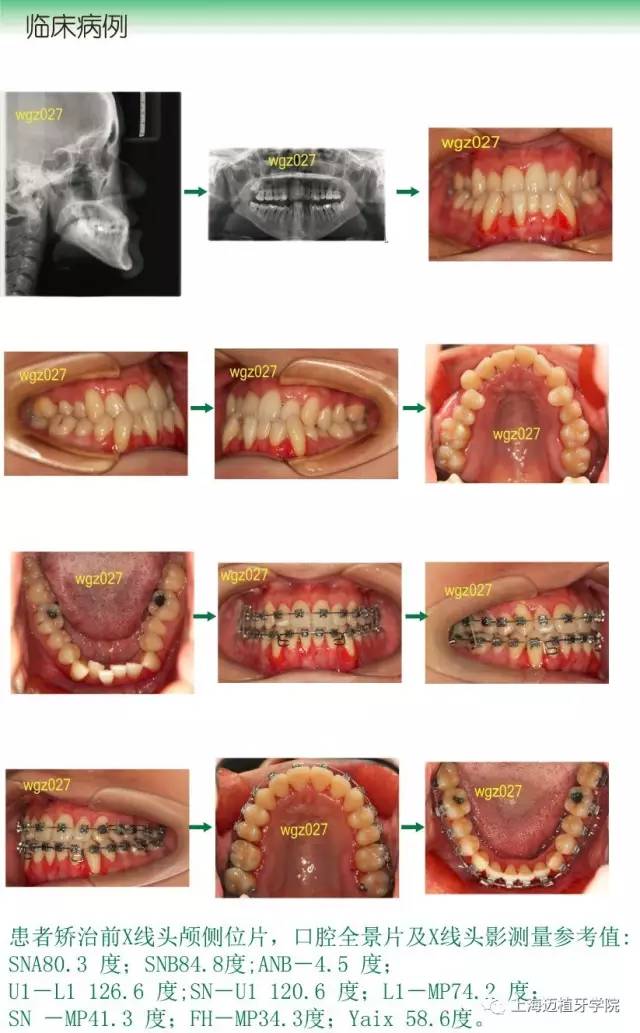

武廣增系統(tǒng)化正畸課程

2017 上海